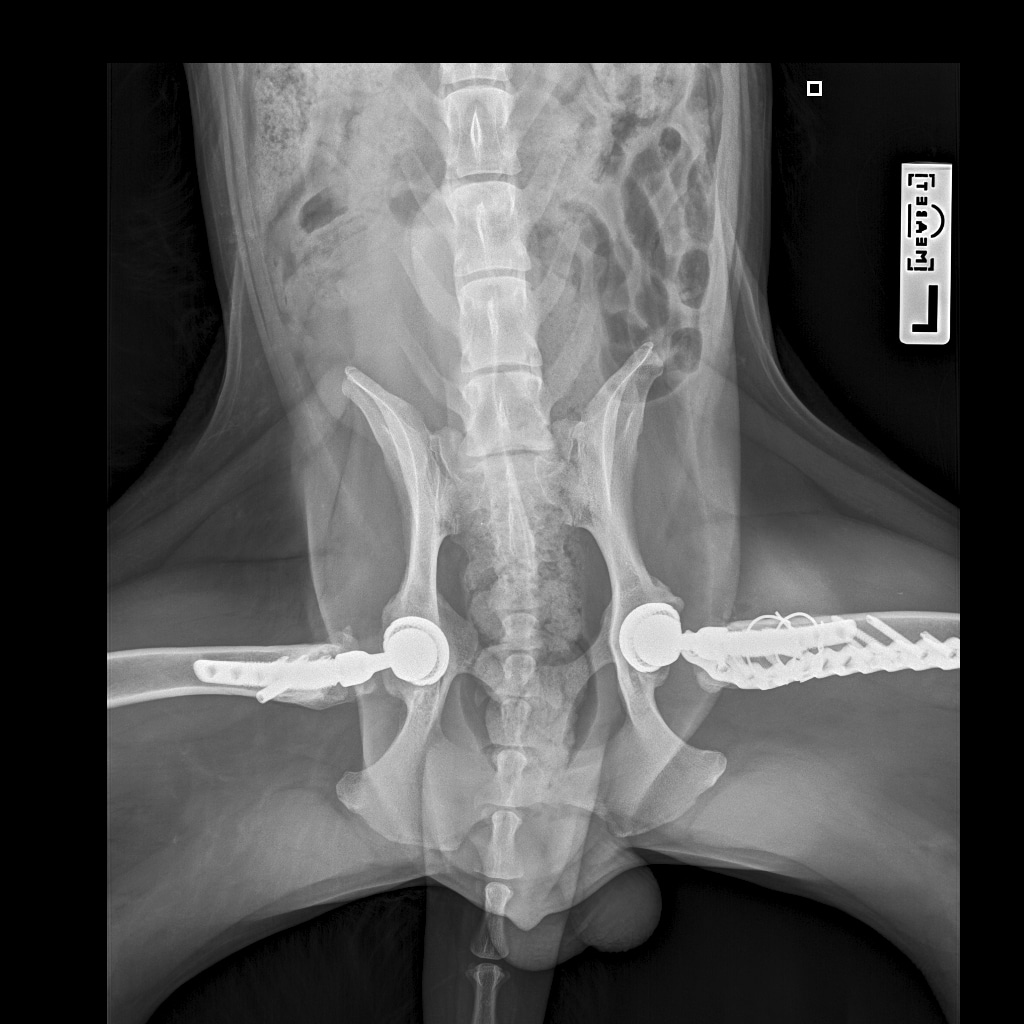

E358D56E-67BF-4D4C-B3F0-BF8F4089D7A2.jpeg

767DD36C-E2E2-41FB-9CCF-6940421D2BB2.jpeg

701487DA-D6D9-4CE0-B18B-EEB120E78EF2.jpeg

Мы ничего не оплачивали. Все включено.

За время противовоспалительной терапии снизилось воспаление и в левом тазобедренном суставе, но увы, форма головки бедренной кости и состояние шейки бедра , лучше не стали:(((

Операция однозначно нужна.

Снимки столь качественные, что их можно в учебник